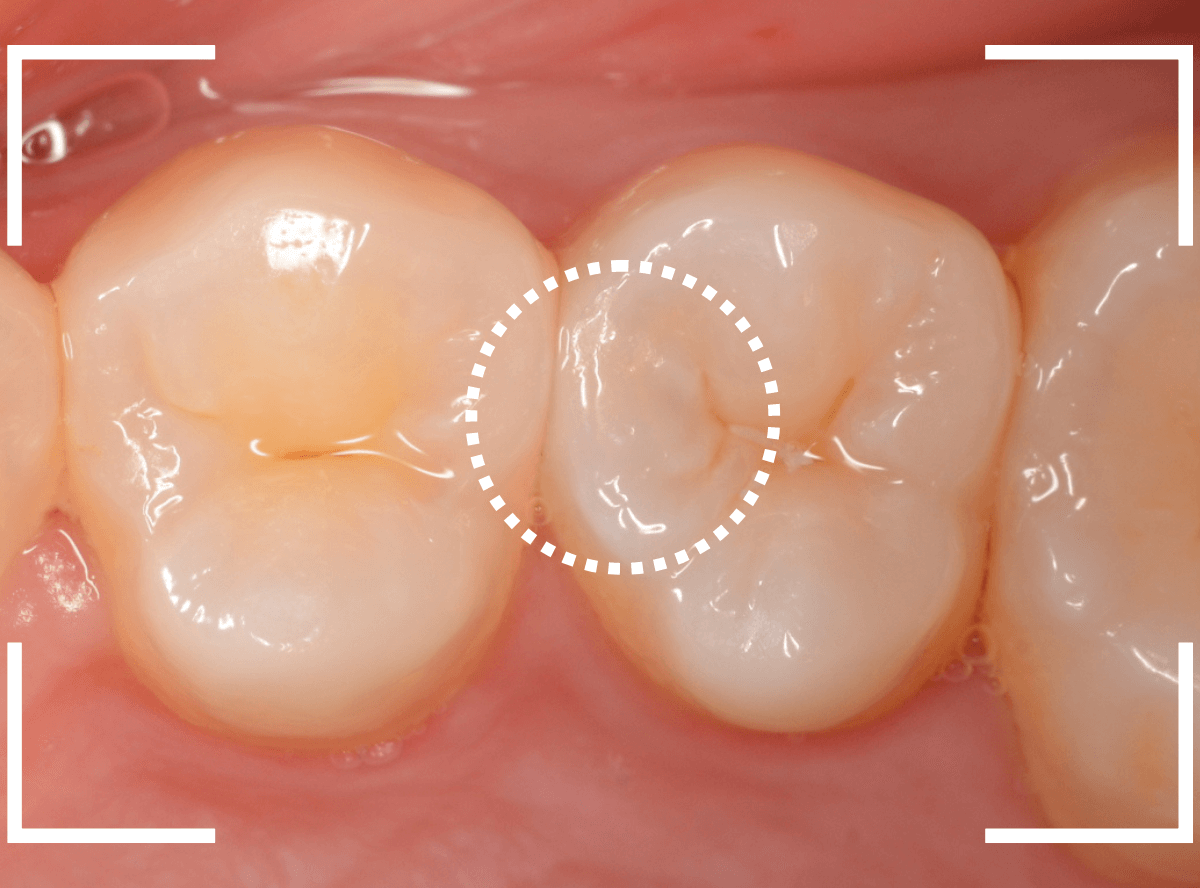

Case.16 白濁でわかる虫歯

他の歯の治療希望で来院された患者さんです。

お口の中全体をチェックしていると、白濁した歯が見つかりました。

中で深い虫歯になっている可能性が高いです。